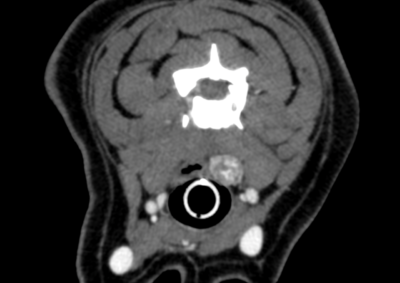

腫瘍外科 注意 ボタンをクリックした先に、治療中および手術中の画像が説明で使用されている場合がございます。 そのような画像に弱い方は閲覧なさらないようお願いいたします。 腫瘍外科 肝葉切除術 腫瘍外科 健康診断で発見された犬の甲状腺腫瘍 腫瘍外科 爪床腫瘍(扁平上皮癌) 腫瘍外科 肝葉切除(内側左葉) 救急・集中治療腫瘍外科 犬の巨大乳腺腫瘍 腫瘍外科 頭部肥満細胞腫 腫瘍外科 半側骨盤切除術 Hemi-Pelvectomy 腫瘍外科 Total Hemi-Pelvectomy 半側骨盤切除術 腫瘍外科 胃腺癌 胃部分切除 軟部組織外科腫瘍外科 両側甲状腺腫瘤切除、甲状腺濾胞腺癌 軟部組織外科腫瘍外科 右下顎骨切除 下顎悪性黒色腫 軟部組織外科腫瘍外科 肛門嚢アポクリン腺癌 右肛門嚢腫瘤 腰下リンパ節切除 <1234567> 症例カテゴリー 放射線治療整形外科軟部組織外科脳神経外科内科腫瘍外科救急・集中治療リハビリテーション科腫瘍内科内視鏡科脳神経科呼吸器外科中医・漢方猫の腎移植循環器科